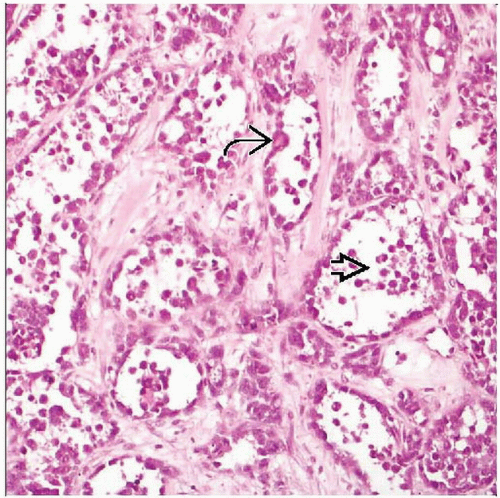

Alveolar Rhabdomyosarcoma, Magnification 20. Dyshesive And Infiltrative

www.researchgate.net

www.researchgate.net

rhabdomyosarcoma alveolar infiltrative magnification

(A) Histological Appearance Of Alveolar Rhabdomyosarcoma: Fibrous

www.researchgate.net

www.researchgate.net

alveolar rhabdomyosarcoma fibrous histological connective septa forming

(A) Histological Appearance Of Alveolar Rhabdomyosarcoma: Fibrous

www.researchgate.net

www.researchgate.net

alveolar rhabdomyosarcoma histological fibrous septa connective figure forming findings implications prognostic pseudo